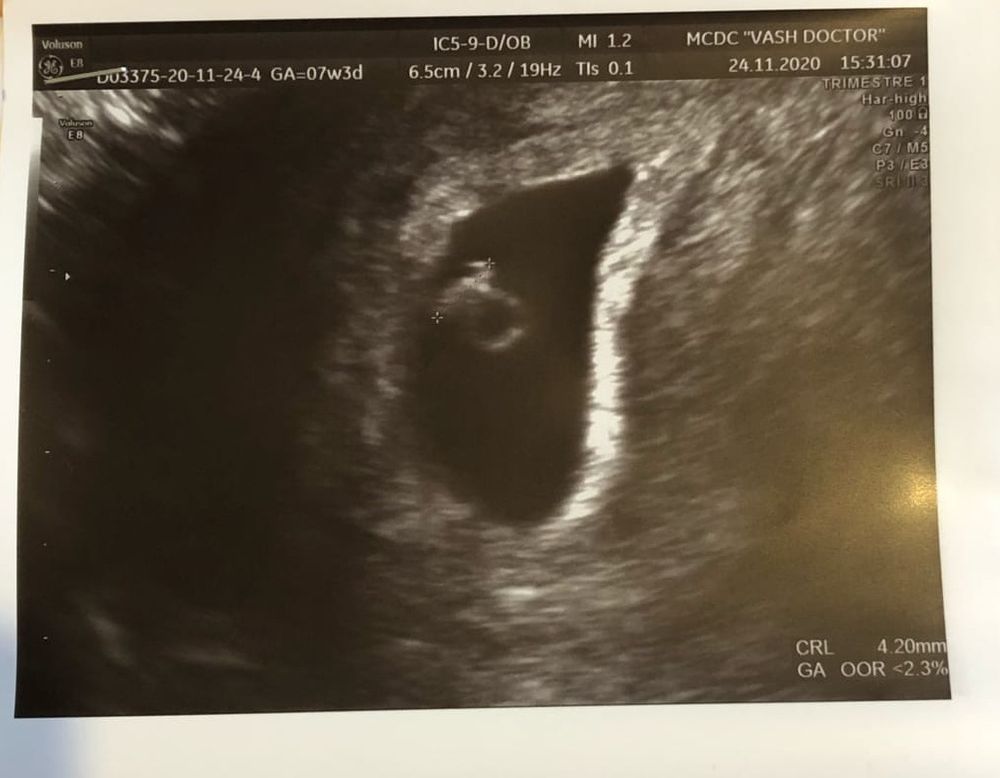

УЗИ второе уже)))Девочки подскажите кто там сидит по Рамзи))

Вчера по М 7 недель 3 дня плодовое 26,2, КТР 4,2, ЖМ 3,2, ЧСС +)) 5-6 неделек поставили, я на больше и не рассчитывала) Ведь тест запаласил на 5 день задержки)

Девочки и кто там сидит по методу Рамзи? вчера читала читала так ничего и не поняла)))УЗИ трансвагинально))) Просто интересно) кольцо на веревочке мне показывает что третья будет девочка)

По Рамзи мальчик, но у меня этот метод не совпал)

Мальчик по Рамзи